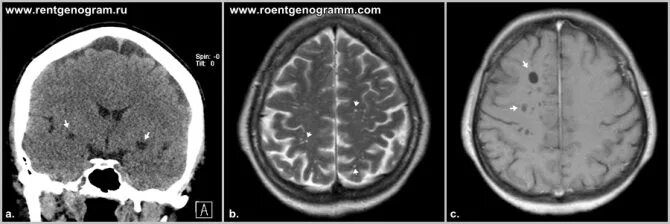

Что значит расширенные периваскулярные пространства